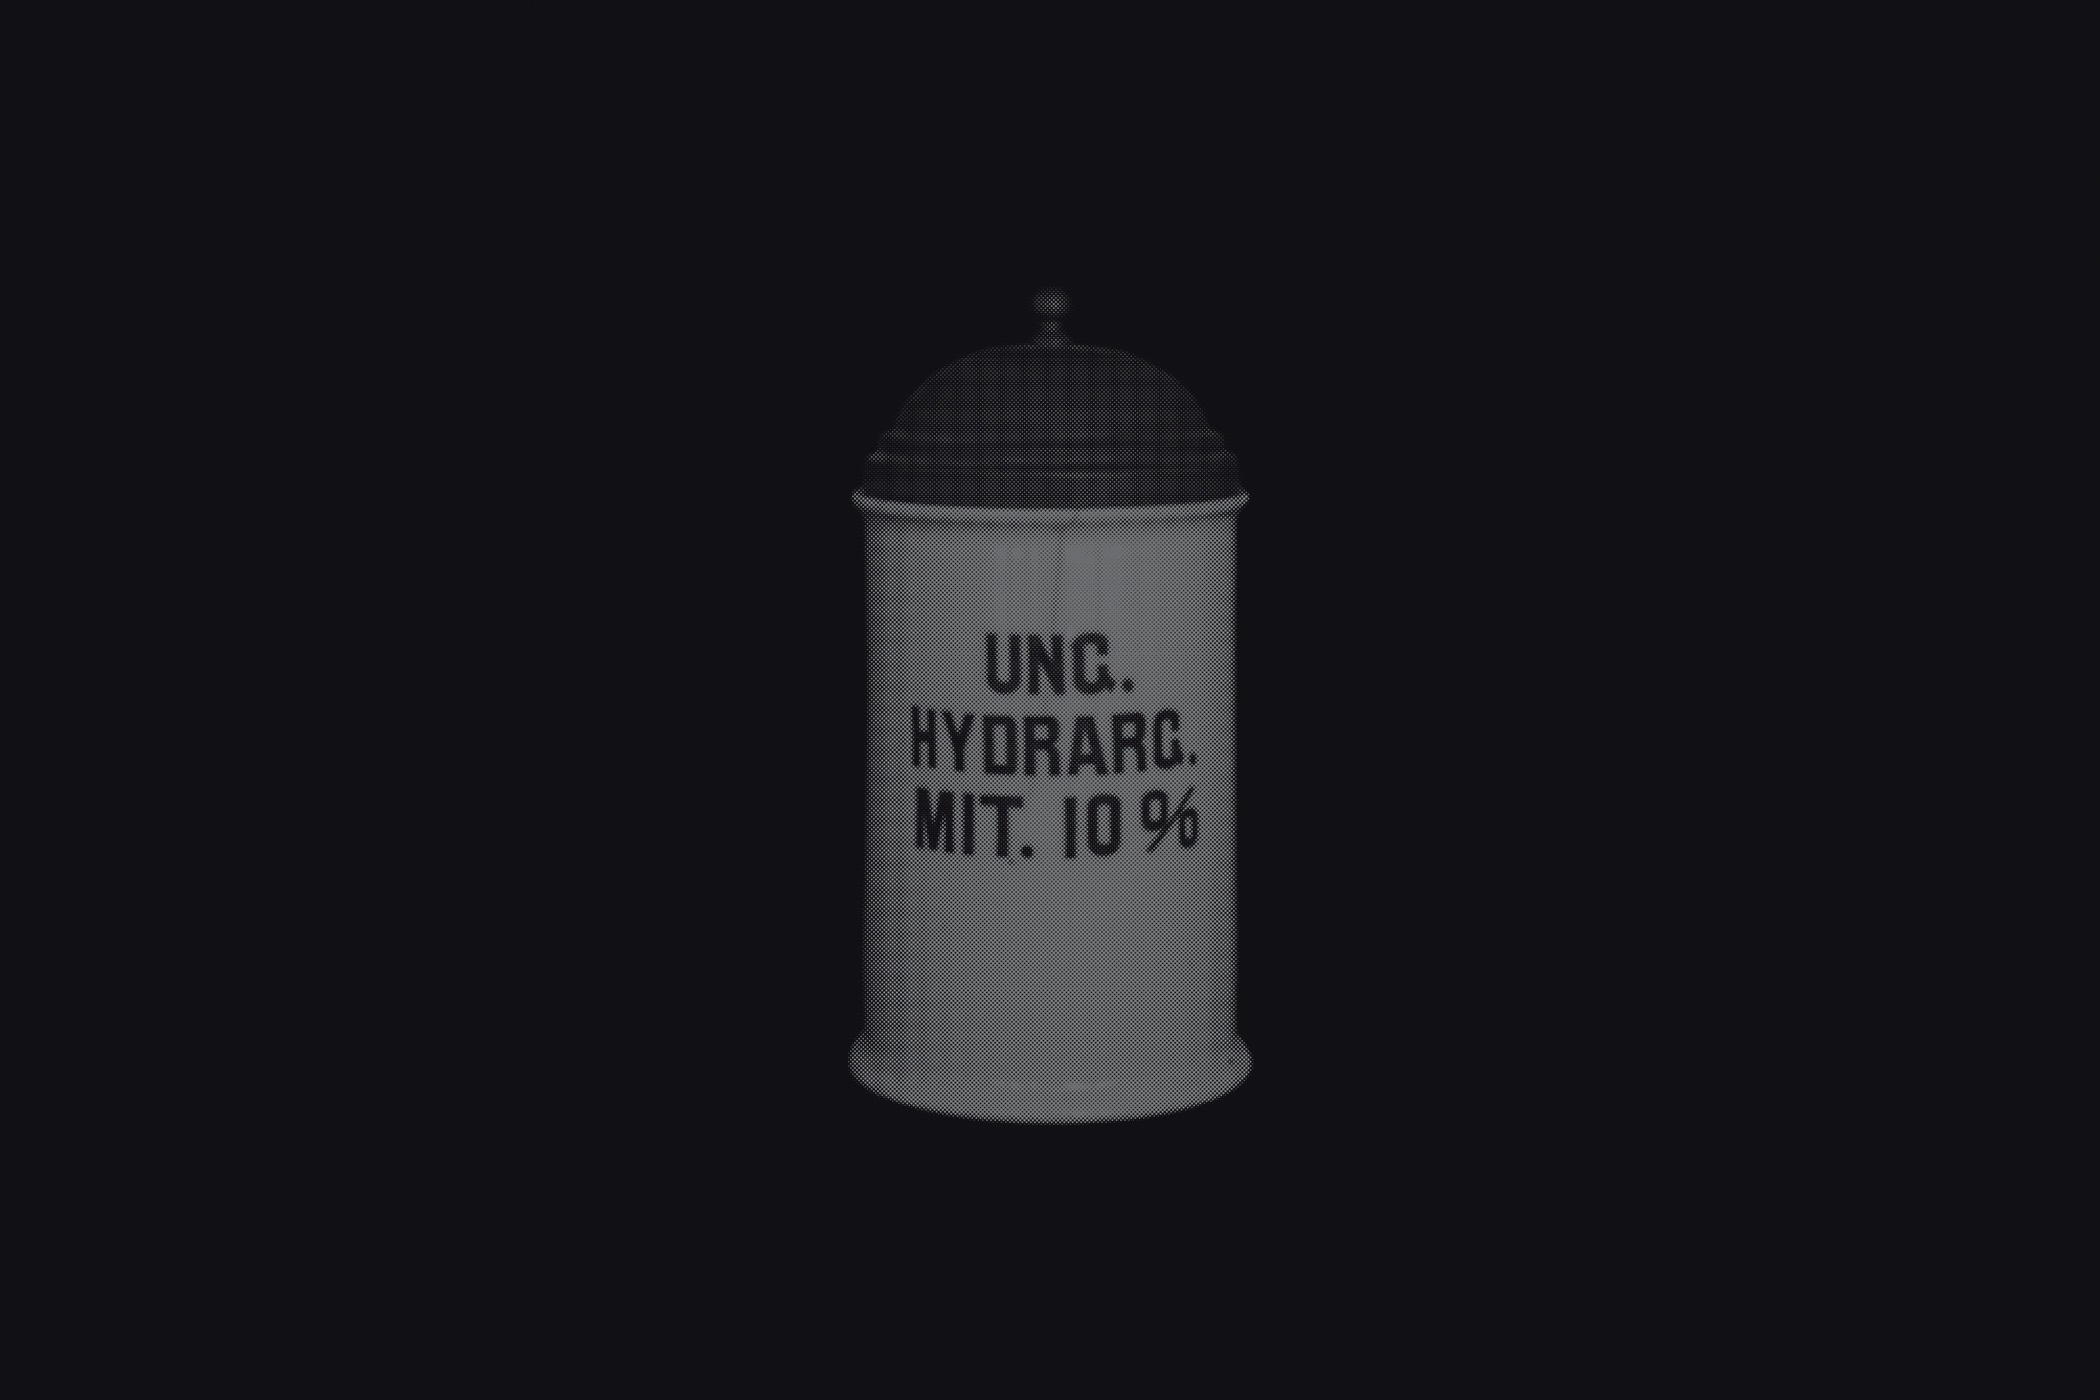

The first series draws from the collection of the Historical and Maritime Museum of Istria, featuring photographs of ceramic and glass apothecary jars transferred onto black paper using silkscreen printing. Instead of traditional ink, the prints were made with powdered active pharmaceutical substances, resulting in faint, almost ghostly images that echo the fragility and ephemerality of the source material.

The first series draws from the collection of the Historical and Maritime Museum of Istria, featuring photographs of ceramic and glass apothecary jars transferred onto black paper using silkscreen printing. Instead of traditional ink, the prints were made with powdered active pharmaceutical substances, resulting in faint, almost ghostly images that echo the fragility and ephemerality of the source material.

Untitled (Archive Pharmacy), 2024

screen printing on paper with color obtained from the powder of the active substances of medicines

graphic sheet 70 x 50 cm, framed 70,5 x 50,5 x 3,5 cm

1-20

Untitled (Archive Pharmacy), 2024

screen printing on paper with color obtained from the powder of the active substances of medicines

graphic sheet 70 x 50 cm, framed 70,5 x 50,5 x 3,5 cm